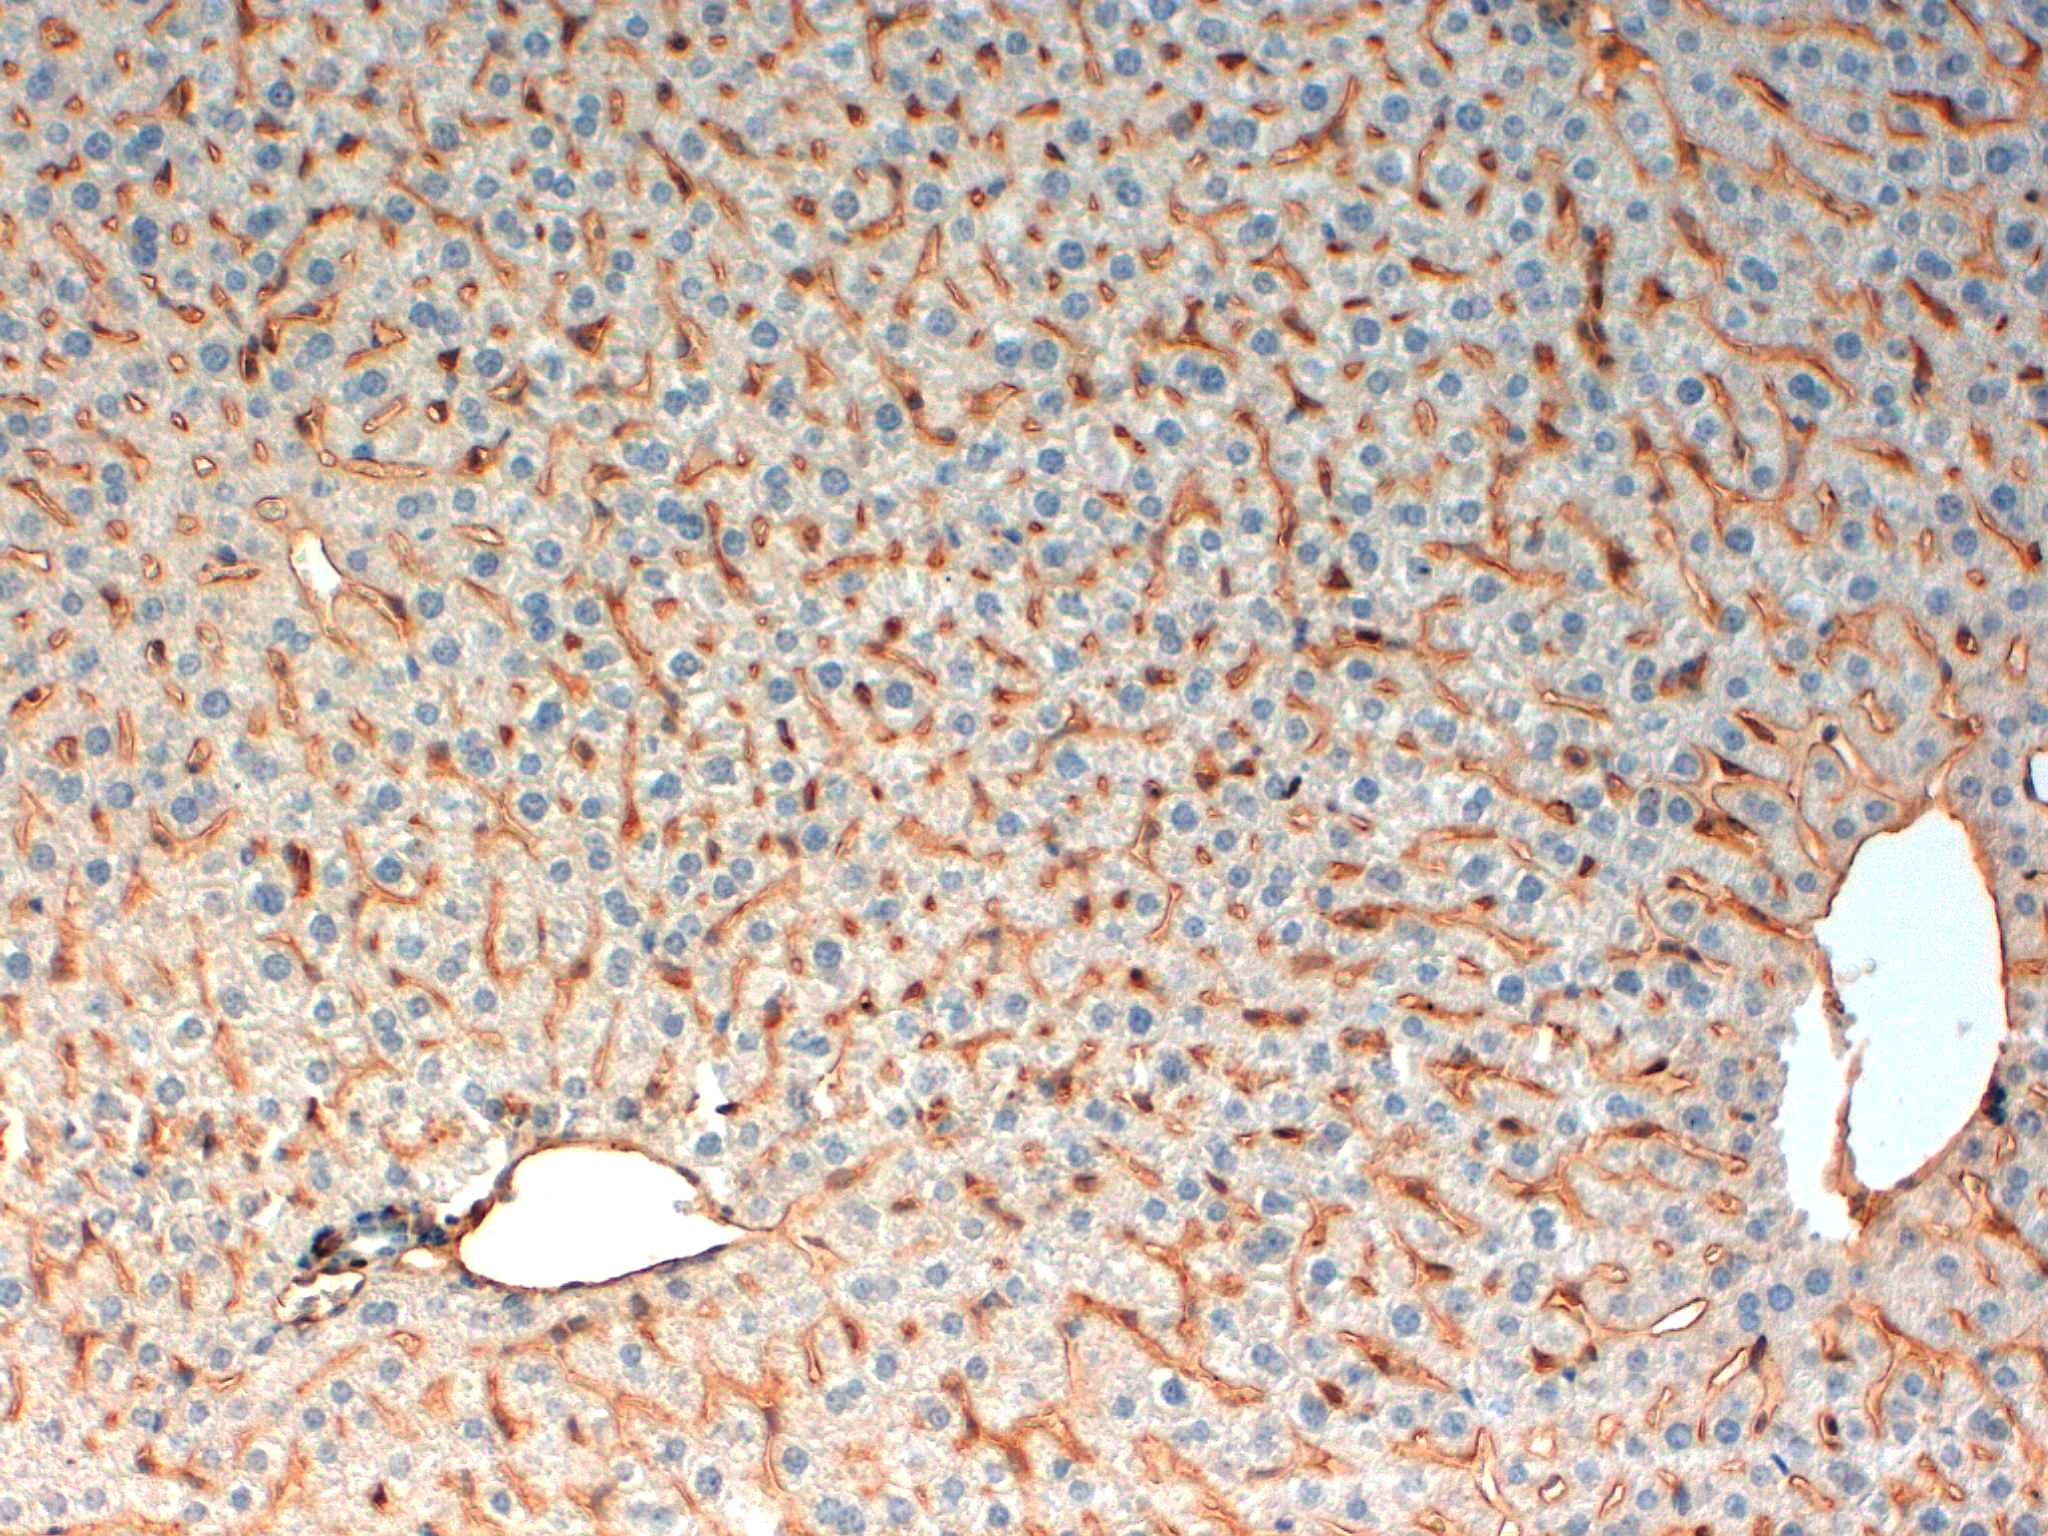

CD31 Mouse Liver 20X